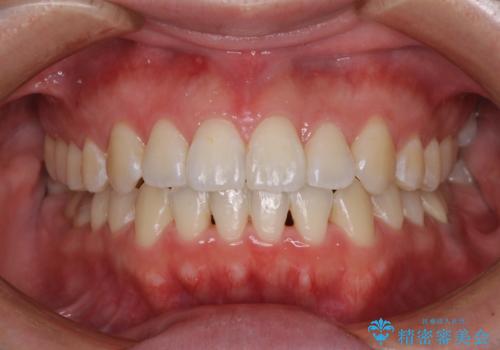

前歯のデコボコを治したい ワイヤー矯正

前歯のがたつき・すれちがい咬合を非抜歯で。流行の、格安マウスピースでは難しい、ワンランク上の治療